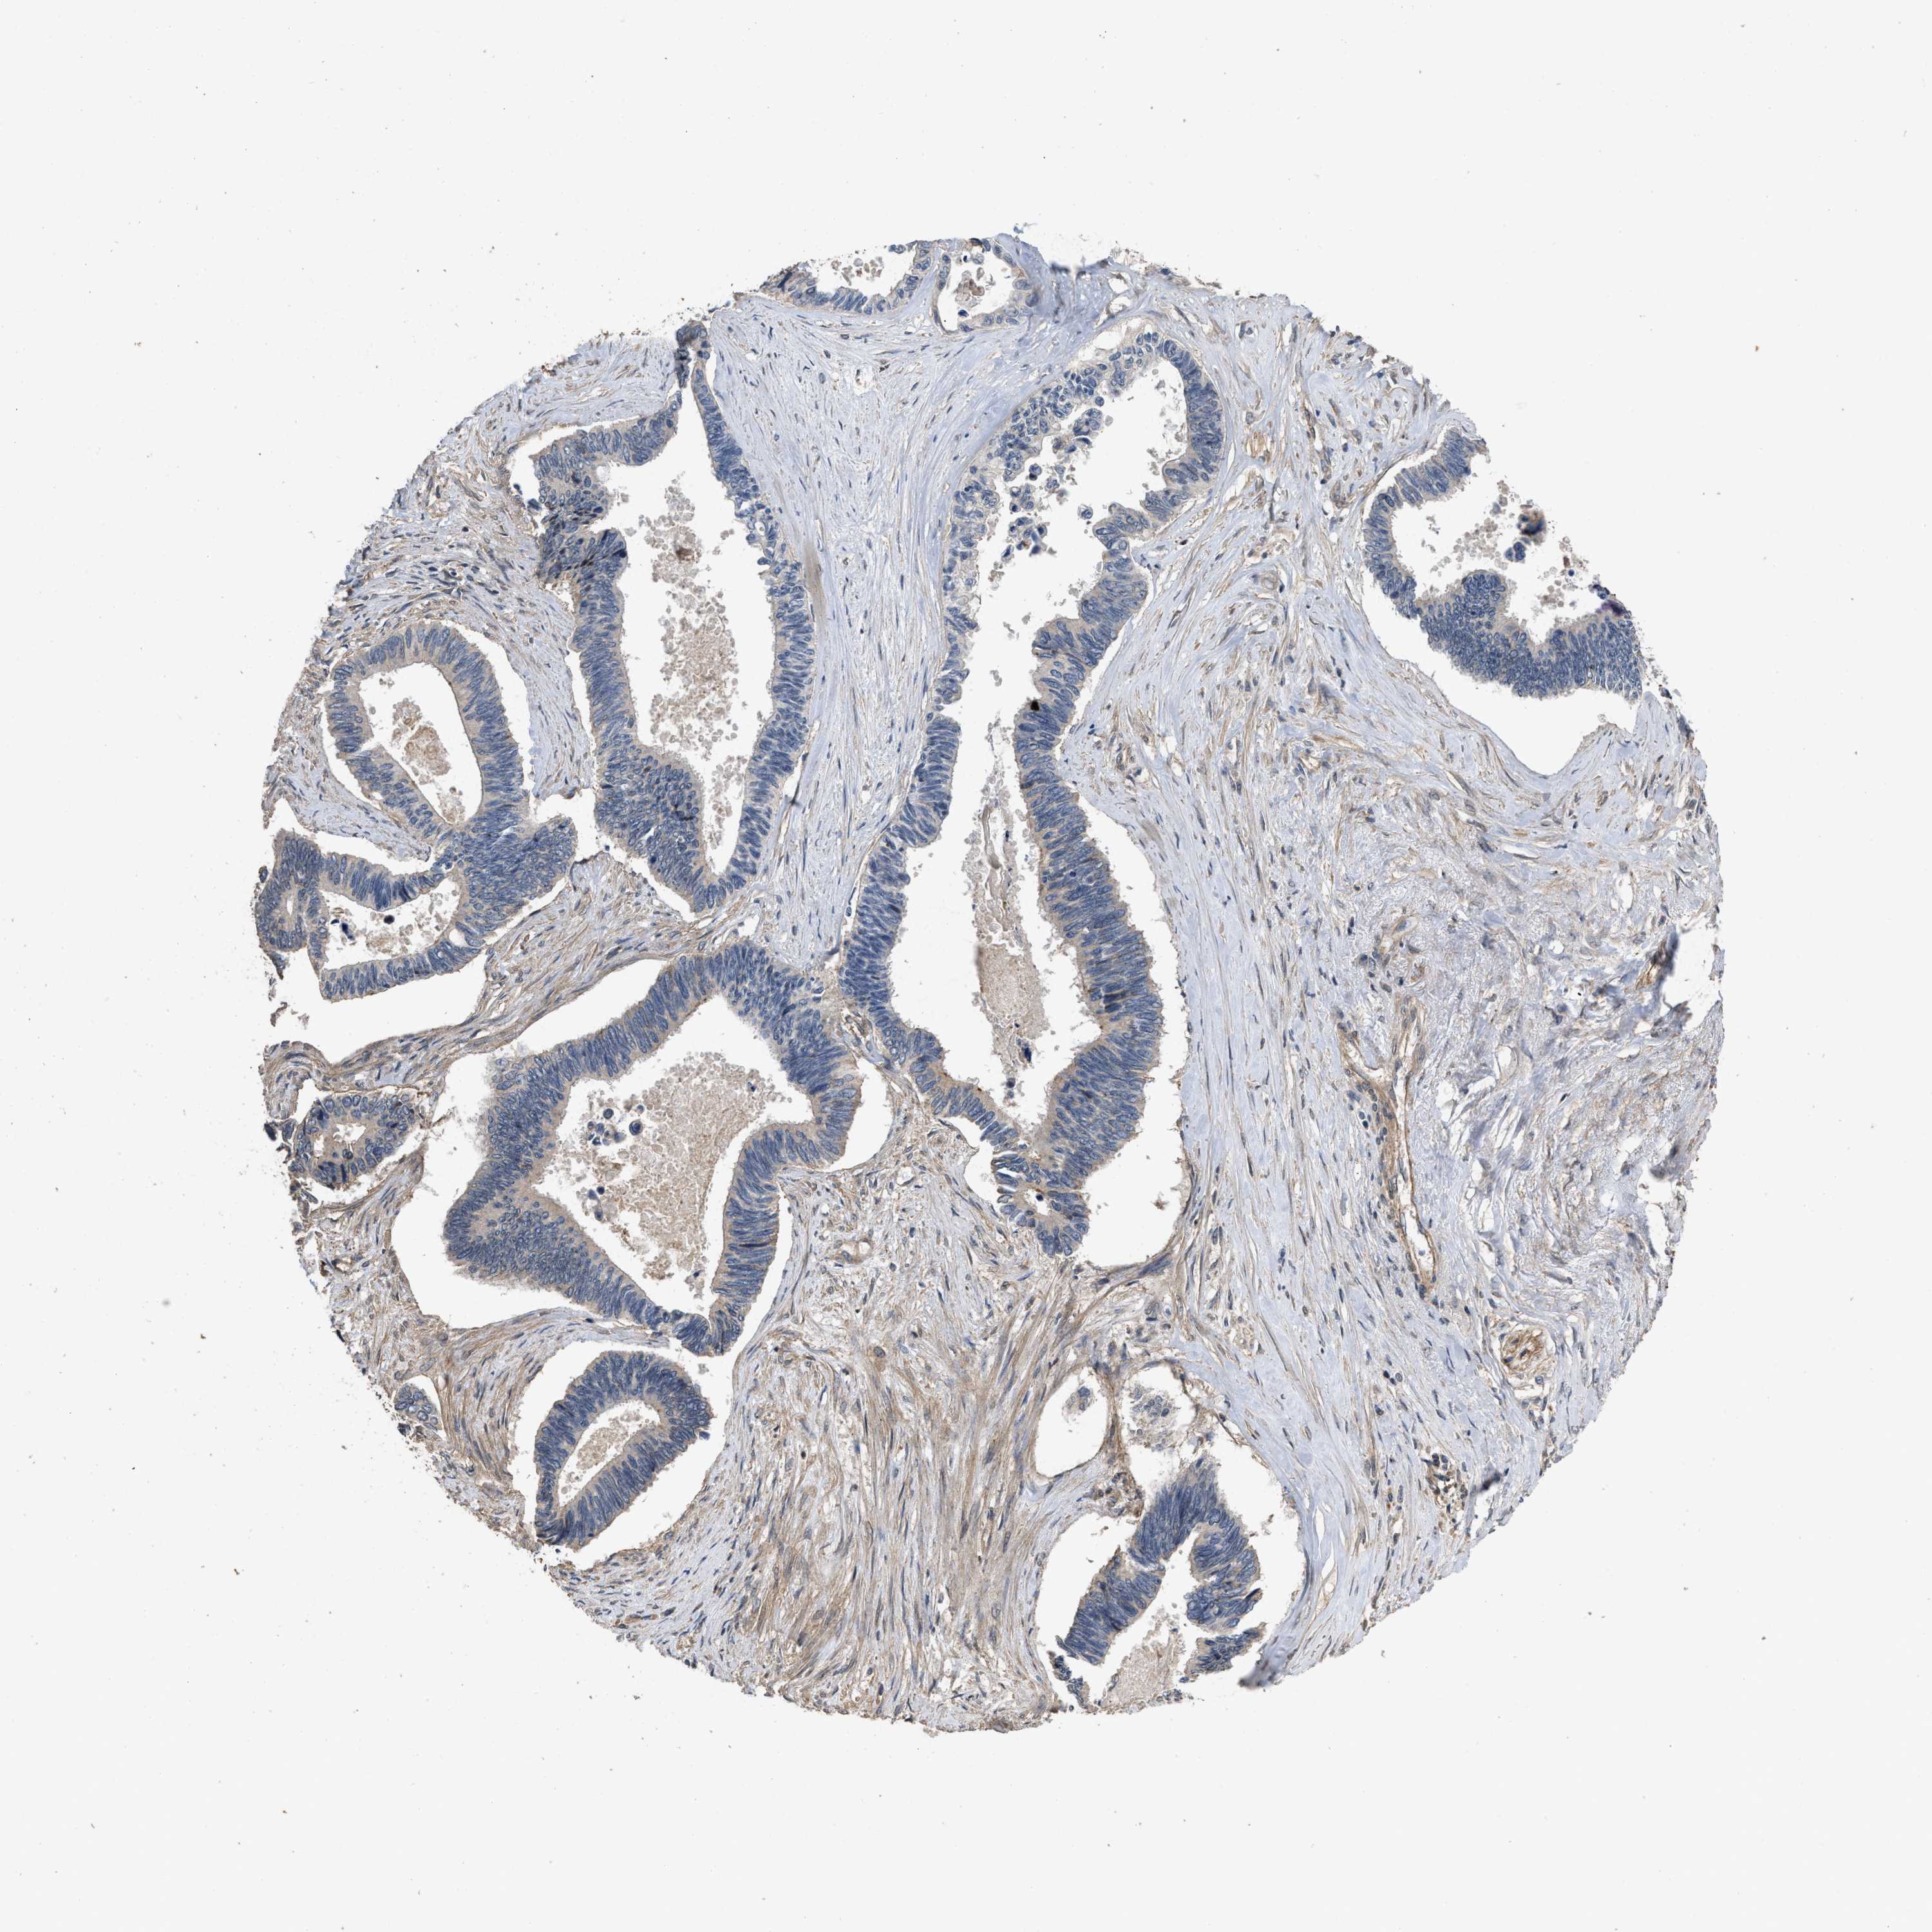

PANCREATIC CANCER - Protein expressioni

A mouse-over function shows sample information and annotation data. Click on an image to view it in a full screen mode. Samples can be filtered based on level of antibody staining by selecting one or several of the following categories: high, medium, low and not detected. The assay and annotation is described here.

Note that samples used for immunohistochemistry by the Human Protein Atlas do not correspond to samples in the TCGA dataset.

Antibody stainingi

Antibody staining in the annotated cell types in the current human tissue is reported as not detected, low, medium, or high, based on conventional immunohistochemistry profiling in selected tissues. This score is based on the combination of the staining intensity and fraction of stained cells.

Each image is clickable and will lead to virtual microscopy that enables deeper exploration of all samples and also displays staining intensity scores, fraction scores and subcellular localization as well as patient and tissue information for each sample.

Antibody HPA018894

Antibody CAB016348

Staining

High

Medium

Low

Not detected

Intensity

Strong

Moderate

Weak

Negative

Quantity

>75%

75%-25%

<25%

None

Location

Nuclear

Cytoplasmic/membranous

Cytoplasmic/membranous,nuclear

Adenocarcinoma, NOS